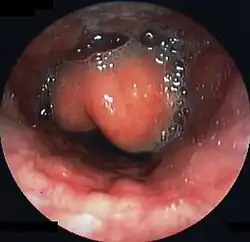

Swollen epiglottis in laryngoscopy

Diagnosis may be confirmed by direct inspection using a laryngoscope, although this may provoke airway spasm.[15] If epiglottitis is suspected, diagnosis is made on basis of fiberoptic laryngoscopy exam carried out in controlled environment like an operating room.[16][17]

CT imaging showing the "halloween sign"

Left column: Normal epiglottis. Right column: Epiglottitis.